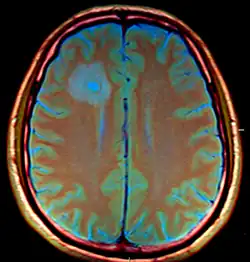

MRI (T1 with contrast) showing the ring-enhancing lesion. From a rare case report of an abscess formed as a complication of the CSF shunt. Jamjoom et al., 2009.[1]

The diagnosis is established by a computed tomography (CT) (with contrast) examination. At the initial phase of the inflammation (which is referred to as cerebritis), the immature lesion does not have a capsule and it may be difficult to distinguish it from other space-occupying lesions or infarcts of the brain. Within 4–5 days the inflammation and the concomitant dead brain tissue are surrounded with a capsule, which gives the lesion the famous ring-enhancing lesion appearance on CT examination with contrast (since intravenously applied contrast material can not pass through the capsule, it is collected around the lesion and looks as a ring surrounding the relatively dark lesion). Lumbar puncture procedure, which is performed in many infectious disorders of the central nervous system is contraindicated in this condition (as it is in all space-occupying lesions of the brain) because removing a certain portion of the cerebrospinal fluid may alter the concrete intracranial pressure balances and causes the brain tissue to move across structures within the skull (brain herniation).[14]

Ring enhancement may also be observed in cerebral hemorrhages (bleeding) and some brain tumors. However, in the presence of the rapidly progressive course with fever, focal neurologic findings (hemiparesis, aphasia etc.) and signs of increased intracranial pressure, the most likely diagnosis should be the brain abscess.[15]